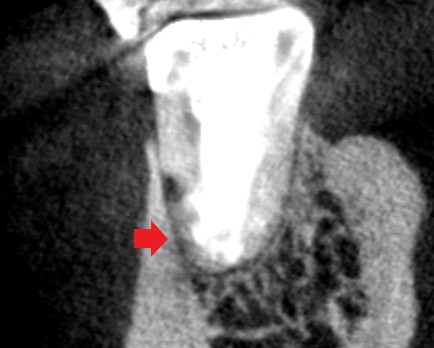

初診時の下顎第一大臼歯遠心根の冠状断のCT画像です。

赤い矢印の先に影がみられ、手術で斜めに根を切断した先の根が切りきれていないように見えます。